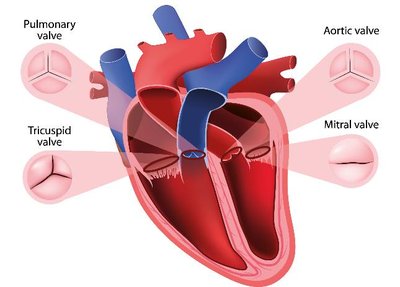

Example: The heart's structure (chambers, valves) enables its function (pumping blood in one direction).

Cardiovascular System: Heart, blood vessels – transport of nutrients and gases.